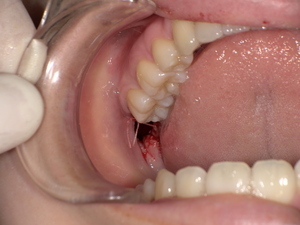

組織検査(生検)が必要なケースとは?

-

白斑が厚く、患部が硬い、出血しやすい

痛みが強く、潰瘍がある

がん化のリスクを排除したい場合

このような場合には粘膜の一部を採取する生体検査(生検)が行われます。

【がん化の危険性】口腔扁平苔癬は口腔がんになる可能性がある?

がん化リスクはどのくらい?

口腔扁平苔癬のがん化率は文献によって異なりますが、0.5~2%程度と報告されています。長期・重症病変や潰瘍形成のある例では注意が必要です。

観察・経過観察が必要な理由

病変ががん化している兆し(硬さ、色の変化、潰瘍化)が現れる場合があるので、定期的な診察と写真記録によるモニタリングが推奨されます。また自己チェック法として、鏡を使用して病変の変化を確認する習慣も有効です。